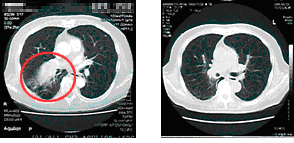

仅治疗三个月后,肿块就缩小了3/4,让马先生最满意的是,化疗后的反应竟然不是很严重。马先生说,“我刚到广州中医药大学金沙洲医院肿瘤综合诊疗中心时,因为咳嗽没办法说话,睡觉都成问题,特别困时仅能趴在桌上小憩,每15分钟就咳醒一次。多亏广州中医药大学金沙洲医院肿瘤综合诊疗中心这种独特的绿色化疗的治疗,不但治好了我的咳嗽,也没给我的身体带来什么副作用。”

治疗前 治疗后